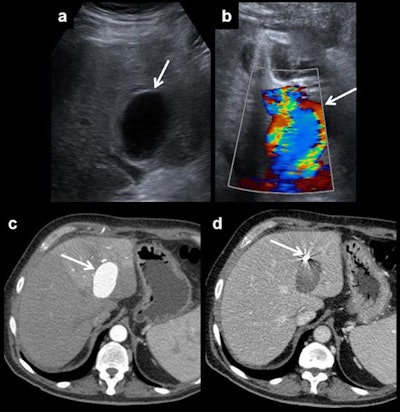

Hepatic artery pseudoaneurysm. Pseudoaneurysms can be discovered using ultrasound (a). It shows a characteristic appearance on Doppler ultrasound due to the turbulent forward and backward flow (b). Arterial phase CT shows arterial enhancement of the pseudoaneurysm (c). A coil is placed to block entry to the bloodstream and to prevent rupture (d).Usual post-transplantation findings include right-sided pleural effusion, ascites, perihepatic hematoma, and periportal edema. All of them should resolve in the first weeks after surgery.